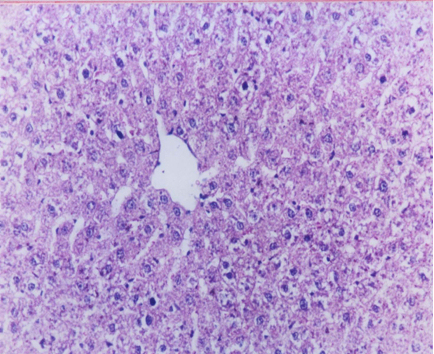

Histopathological results

Our results (Figure 1 [Fig. 1], Figure 2 [Fig. 2], Figure 3 [Fig. 3], Figure 4 [Fig. 4], Figure 5 [Fig. 5], Figure 6 [Fig. 6], Figure 7 [Fig. 7]) revealed that treatment of the PC group with FO or OO supplemented with vitamins E & C led to the best improvement. The histopathological investigation showed apparently normal hepatocytes.

Little data are available on the effect of supplemented diets with vitamin E and C on intoxicated rat livers with CCl4. The histological results confirmed that the hepatically injured rats with CCl4 and fed on supplemented FOEC or OOEC showed apparently normal hepatocytes.